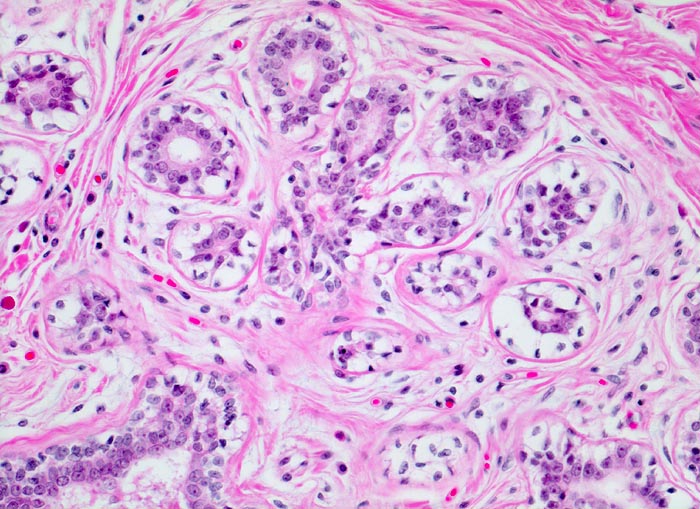

Makroskopisch bildet das mastopathisch veränderte Parenchym weisse kompakte fibröse Areale mit Einschluss von Zysten, welche oftmals eingedicktes Sekret enthalten. Neben einer Stromafibrose und zystisch ausgeweiteten Gängen mit Sekretretention findet sich oft eine unterschiedlich ausgeprägte intraduktale Proliferation von luminalen und basalen Epithelzellen. Nicht selten liegen als Begleitbefund kleine Fibroadenome, eine sklerosierende Adenose oder Gänge mit apokriner Metaplasie vor. Oftmals finden sich auch intraduktale Mikroverkalkungen. Die duktale Hyperplasie ist im Gegensatz zur atypischen Hyperplasie und zum Carcinoma in situ charakterisiert durch eine bunte, ungeordnete Proliferation ungleich grosser polygonaler bis spindeliger Zellen mit Ausbildung von schlitzförmigen Hohlräumen oder dünnen epithelialen Brücken. Die euchromatischen Kerne variieren in Grösse, Form und Lagerung. Bei paralleler Lagerung der Kerne entsteht der Eindruck eines Strömens und Fliessens der Zellen. Das duktale Carcinoma in situ ist von gutartigen intraduktalen Epithelproliferationen abzugrenzen aufgrund seiner Monomorphie (> 5185), Hyperchromasie der Zellkerne und starrer geometrischer Muster (runde scharf begrenzte wie ausgestanzte Lumina (> 5184), breite Brücken und Bögen, Mikropapillen). Eine intraduktale Epithelproliferation mit Atypie wird dann diagnostiziert, wenn nur ein Teil der Gänge oder Läppchen die typischen Veränderungen eines Carcinoma in situ zeigt. Die Abgrenzung der atypischen Hyperplasie von der Hyperplasie ohne Atypie erfolgt aufgrund qualitativer Merkmale und die Abgrenzung der Hyperplasie mit Atypie vom Carcinoma in situ aufgrund quantitativer Merkmale.

• Ausgeprägte Fibrose und zystisch erweiterte Gangstrukturen in organoider Anordnung.

• Herdförmig apokrine Metaplasie des Drüsenepithels: hochprismatische Zellen mit sehr reichlichem feingranulärem eosinophilem Zytoplasma und runden Kernen.

• Alle Drüsen zeigen eine erhaltene äussere abgeflachte Myoepithelschicht mit hellem Zytoplasma.